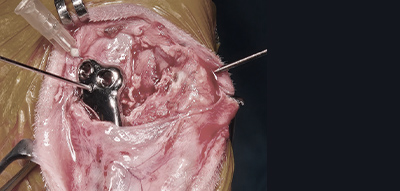

근육・힘줄을 최대한 보존하는 최소 침습 TPLO 수술 시행하며 관절경을 통해 관절을 열지 않고 수술 진행하기때문에 환자의 통증을 최소화합니다.

최소 침습 TPLO 수술 시행

동물병원 최고가 4K 스톨츠 관절경을 통해

관절을 열지 않고 수술 진행하여 통증 최소화

최소절개 TPLO 수술

예은동물의료센터에서는 근육・힘줄을 최대한 보존하는 최소 침습 TPLO 수술 시행하며

관절경을 통해 관절을 열지 않고 수술을 진행하기때문에 환자의 통증을 최소화합니다.

관절경을 이용한 수술

관절경을 이용한 수술은 최소 통증, 빠른 회복이 큰 장점으로 근육・힘줄을 최대한 보존하는 최소 침습 수술 시행합니다.